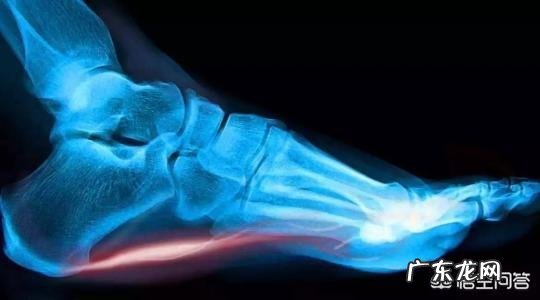

突然脚后跟疼 , 什么情况?突然脚后跟痛一般都是由两种疾病导致 。体重较大 , 过度体育锻炼 , 重体力劳动的人发病率更高 。

跟痛症 。

跟痛症是一种多种原因导致的慢性疾病 。属于一种无菌性炎症 , 行走和站立时 , 疼痛加重 , 症状较重时 , 甚至可导致不敢站立 , 甚至踮脚走路 。经常与跟骨骨刺伴生 。

既往认为跟痛症引起的症状是骨刺导致 。最新研究表明骨刺并不是引起跟痛症的主要原因 。

?跟痛症的定诊一般不需特殊检查 。常规医师查体加上放射线片即可定诊

跖筋膜炎是一种跖筋膜的急、慢性损伤或长期劳损导致的慢性无菌性炎症 。

典型症状是在晨起或长时间休息后开始站立行走时 , 逐渐出现跟底及足心的疼痛 。